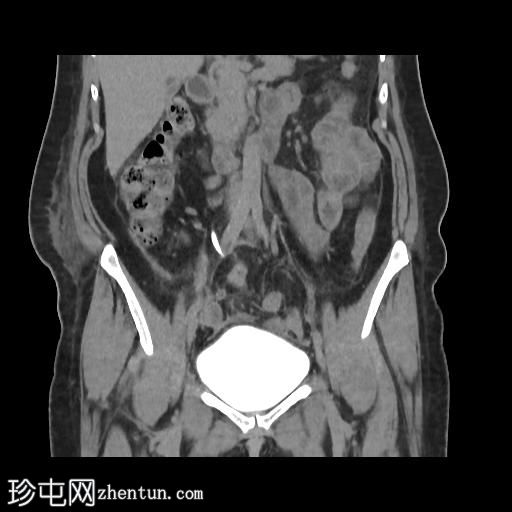

冠状位肾盂排泄期

CT扫描显示:

左侧膀胱后外侧壁完全撕裂,造影剂外渗至盆腔

盆腔内可见少量积液

腹膜脂肪条索状改变,腹膜反折增厚强化,提示盆腔腹膜炎